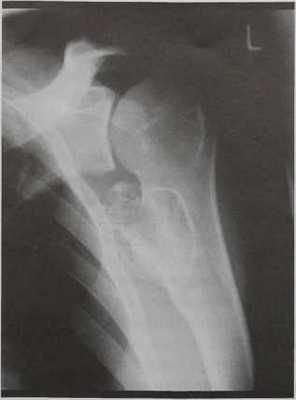

Что покажут рентгеновские снимки костей конечностей при остеохондроме

Остеохондрома ( костно хрящевой экзостооз ). Рентгенологическое исследование в прямой проекции левой плечевой кости у мужчины 23 лет с типичной остеохондромой по типу «цветной капусты» в проксимальной части плечевой кости.